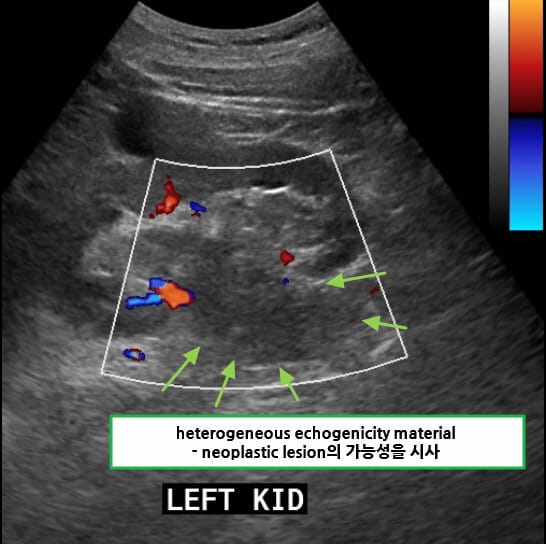

초음파 소견

신세포암(Renal cell carcinoma)은 복부 초음파에서 우연히 발견되는 경우가 많으며, 종괴의 존재 여부와 낭성/고형성 여부를 파악하는 데 유용합니다.

| 🟩 고형 종괴(hyperechoic 또는 isoechoic mass) |

| 주로 신장 실질 내에 존재하는 경계 명확한 고형 병변으로 보이며, 주변 실질에 비해 에코가 높거나 비슷한 양상을 보입니다. |

| 🟩 낭성 병변 내 고형 부위 존재 |

| 복합 낭성 병변의 경우 내부에 고형 부위가 관찰되면 악성 가능성이 높습니다. |

| 🟩 도플러 혈류 증가시 가능성이 높아지나 필수는 아님!!! |

| 병변 내 혈류가 증가되어 있을 경우 악성 가능성을 시사하며, 도플러 검사에서 확인할 수 있습니다. |

| 🟩 신장 외부 돌출 또는 변형 |

| 종양이 신장 피막을 넘어서 돌출되거나, 신장의 외형이 비정상적으로 변형된 경우 진행된 병기 가능성을 고려합니다. |